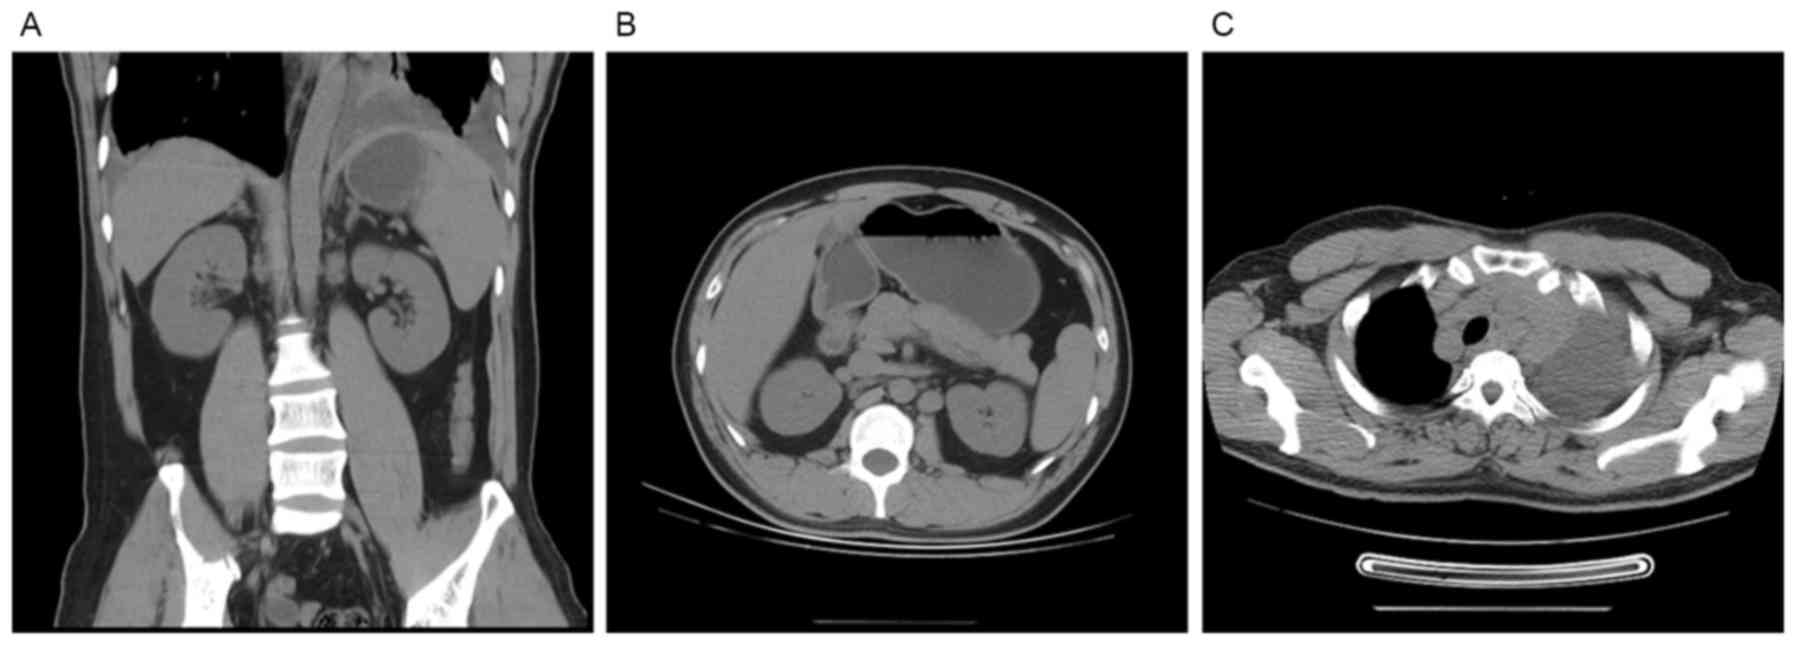

T cell acute lymphoblastic lymphoma complicated with myeloid sarcoma in an adult: A case report

The present case report describes a rare case of T cell acute lymphoblastic lymphoma (T‑LBL) in the lymph node with myeloid sarcoma in the pericardium. A 33‑year‑old Chinese male was admitted to hospital on 4 July 2015 exhibiting a fever and having experienced wheezing and fatigue for the previous 7 days. Routine pathological, computed tomographic, cytological and immunophenotypic observations revealed a diagnosis of T‑LBL in the lymph node on 7 August 2015, without evidence of bone marrow (BM) involvement. The patient received induction chemotherapy for T‑LBL and achieved partial remission. The patient was identified to have multiple serous effusion and analysis of pericardial effusion cells revealed the diagnosis of T‑LBL with extramedullary myeloid sarcoma (without BM involvement) on 25 November 2015. On 30 December 2015, the patient was identified to exhibit proliferation of primary myeloid cells in the peripheral blood and BM, and an abnormal karyotype in BM cells, indicating that the complicated myeloid sarcoma involved the BM. No matched donor was available so the patient received chemotherapy to manage the disease. The patient was discharged on 31 January 2016 and ceased treatment. The patient succumbed on 19 February 2016 at home. To the best of our knowledge, T‑LBL complicated with myeloid sarcoma had not been previously reported in Chinese adult male patients. In addition, the involvement of the BM and aberrant karyotype of the complicated myeloid sarcoma in the patient were rare.